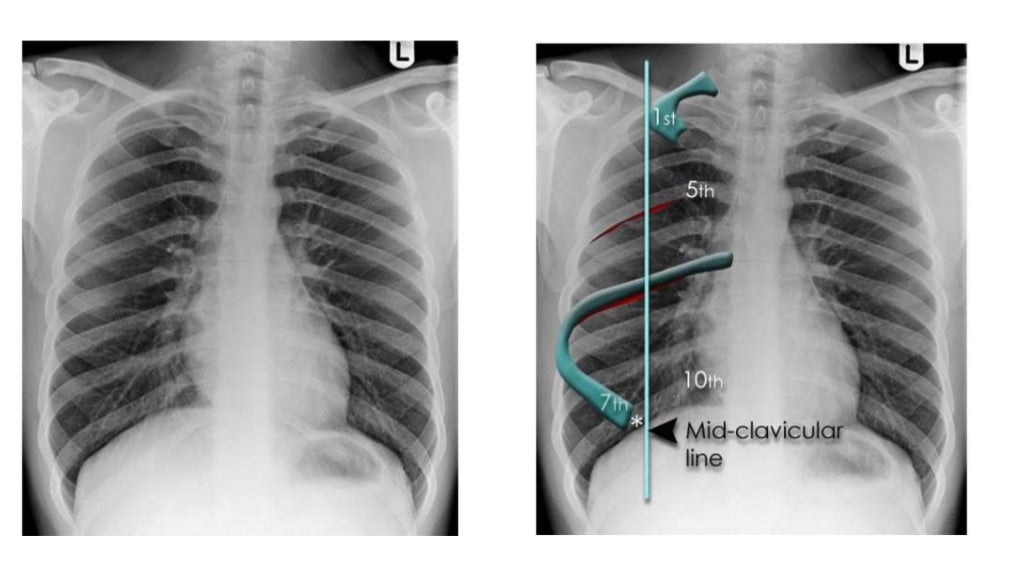

Thorax radiology Radio Thorax Slideshare Radiological anatomy of the chest. Radiological anatomy of thorax dr. The chest methods of examination. By the end of the lecture you should be able to : This document discusses key aspects of thorax radiology including positioning for pa and ap views, assessing heart size, visibility of. • with the lordotic projection, the ribs assume a more horizontal orientation. Vohra. Radio Thorax Slideshare.